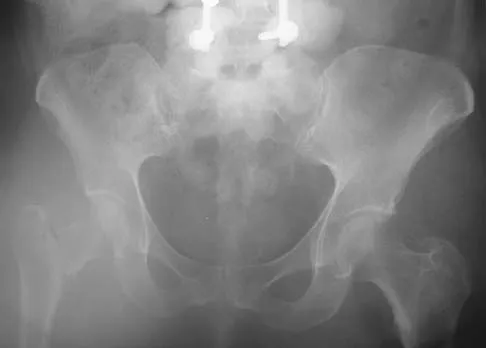

Which of the following choices best describes the fracture pattern shown in Figures 2a through 2c?

Explanation

The fracture pattern shown in the radiographs is a fracture of the posterior column. The only line interrupted on the AP pelvis is the ilioischial line. The obturator oblique view shows that the iliopectineal line is intact as is the outline of the posterior wall. The iliac oblique view shows an interruption of the ilioischial line and an intact anterior wall. Therefore, this fracture is a fracture of the posterior column. Letournel E, Judet R: Fractures of the Acetabulum, ed 2. Berlin, Germany, Springer Verlag, 1993.